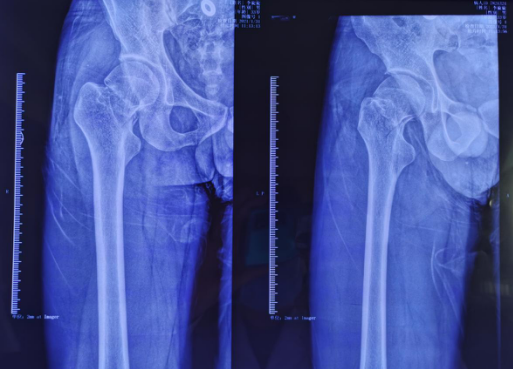

术前影像

这是一位33岁的男性患者,干活时不慎从3米高梯子上摔落,导致“右股骨颈骨折,断端错位”,当地医生建议手术治疗。患者打听后,得知徐州仁慈医院是三级骨科医院,可采用骨科机器人进行微创手术,从老家赶来就诊。

关节科、运动医学科张传开主任给患者完善相关检查,该患者的各项指征符合进行股骨颈骨折机器人手术的要求。